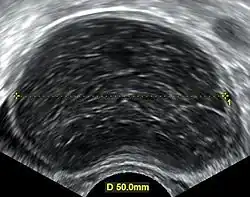

Ovarian cysts are usually diagnosed by pelvic ultrasound, CT scan, or MRI, and correlated with clinical presentation and endocrinologic tests as appropriate.[15] Ultrasound is the most important imaging modality, as abnormalities seen in a CT scan sometimes prove to be normal in ultrasound.[5][8] If a different modality is needed, then MRIs are more reliable than CT scans.[5]

Usually, an experienced sonographer can readily identify benign ovarian cysts, often with a level of accuracy that rivals other approaches.[5]

Follow-up imaging in women of reproductive age for incidentally discovered simple cysts on ultrasound is not needed until 5 cm, as these are usually normal ovarian follicles. Simple cysts 5 to 7 cm in premenopausal females should be followed yearly. Simple cysts larger than 7 cm require further imaging with MRI or surgical assessment. Because they are large, they cannot be reliably assessed by ultrasound alone; it can be difficult to see posterior wall soft tissue nodularity or thickened septation due to limited ultrasound beam penetrance at this size and depth. For the corpus luteum, a dominant ovulating follicle that typically appears as a cyst with circumferentially thickened walls and crenulated inner margins, follow up is not needed if the cyst is less than 3 cm in diameter.[8] In postmenopausal women, any simple cyst greater than 1 cm but less than 7 cm needs yearly follow-up, while those greater than 7 cm need MRI or surgical evaluation, similar to reproductive age females.[16]